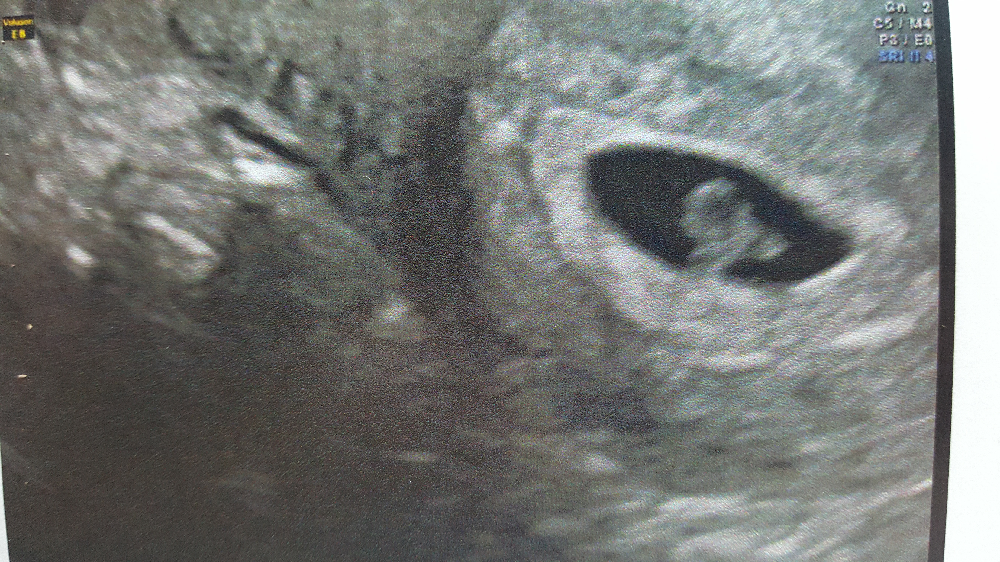

Grossesse intrautérine avec un œuf clair

Sac gestationnel extrautérin La Revue du Praticien

On parle d'œuf clair lorsque l'œuf ne contient aucun embryon : le sac gestationnel est « clair ». Il ne contient ni embryon ni vésicule vitelline.Pour autant, on ne parlera de grossesse arrêtée que lorsque le sac gestationnel aura atteint 25 mm ou plus. S'il est de taille inférieure, il faudra recontrôler, car il est possible qu'il y ait eu erreur dans le calcul de la date de.

La définition. Le sac gestationnel, aussi appelé sac embryonnaire ou ovulaire, est le sac dans lequel se trouve l'embryon. À l'échographie par voie vaginale (dite endovaginale), le sac gestationnel a l'aspect d'un petit point noir, un cercle rempli de noir, et au contour blanc. L'intérieur correspond à la cavité chorionique.